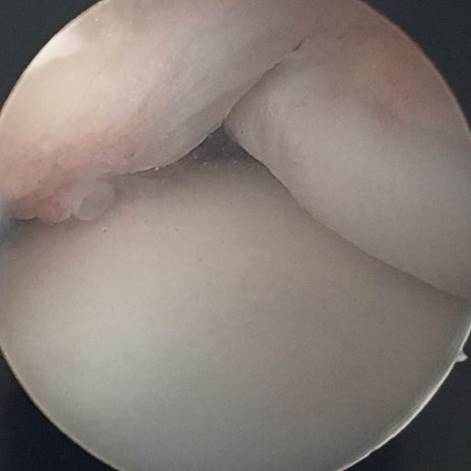

Die Gelenkspiegelung

Die Arthroskopie des oberen Sprunggelenkes ist eine minimal-invasive Operationstechnik, die im Frühstadium der Arthrose zum Einsatz kommt und sehr gute Ergebnisse hervorbringt. Mit nur zwei kleinen Schnitten werden eine Kamera und kleine Instrumente in das Gelenk eingebracht. Die entzündete Gelenkschleimhaut und schmerzhafte Narben, die im Gelenk stören, werden entfernt. Häufig führen Knochennasen zu Bewegungseinschränkungen, die ebenfalls entfernt (reseziert) werden können. Die Beurteilung der Knorpelqualität und der Stabilität des Bandapparates ist ebenfalls möglich. Nach der Operation sollte der Fuß für zwei Wochen mit nur 20 kg teilbelastet werden.